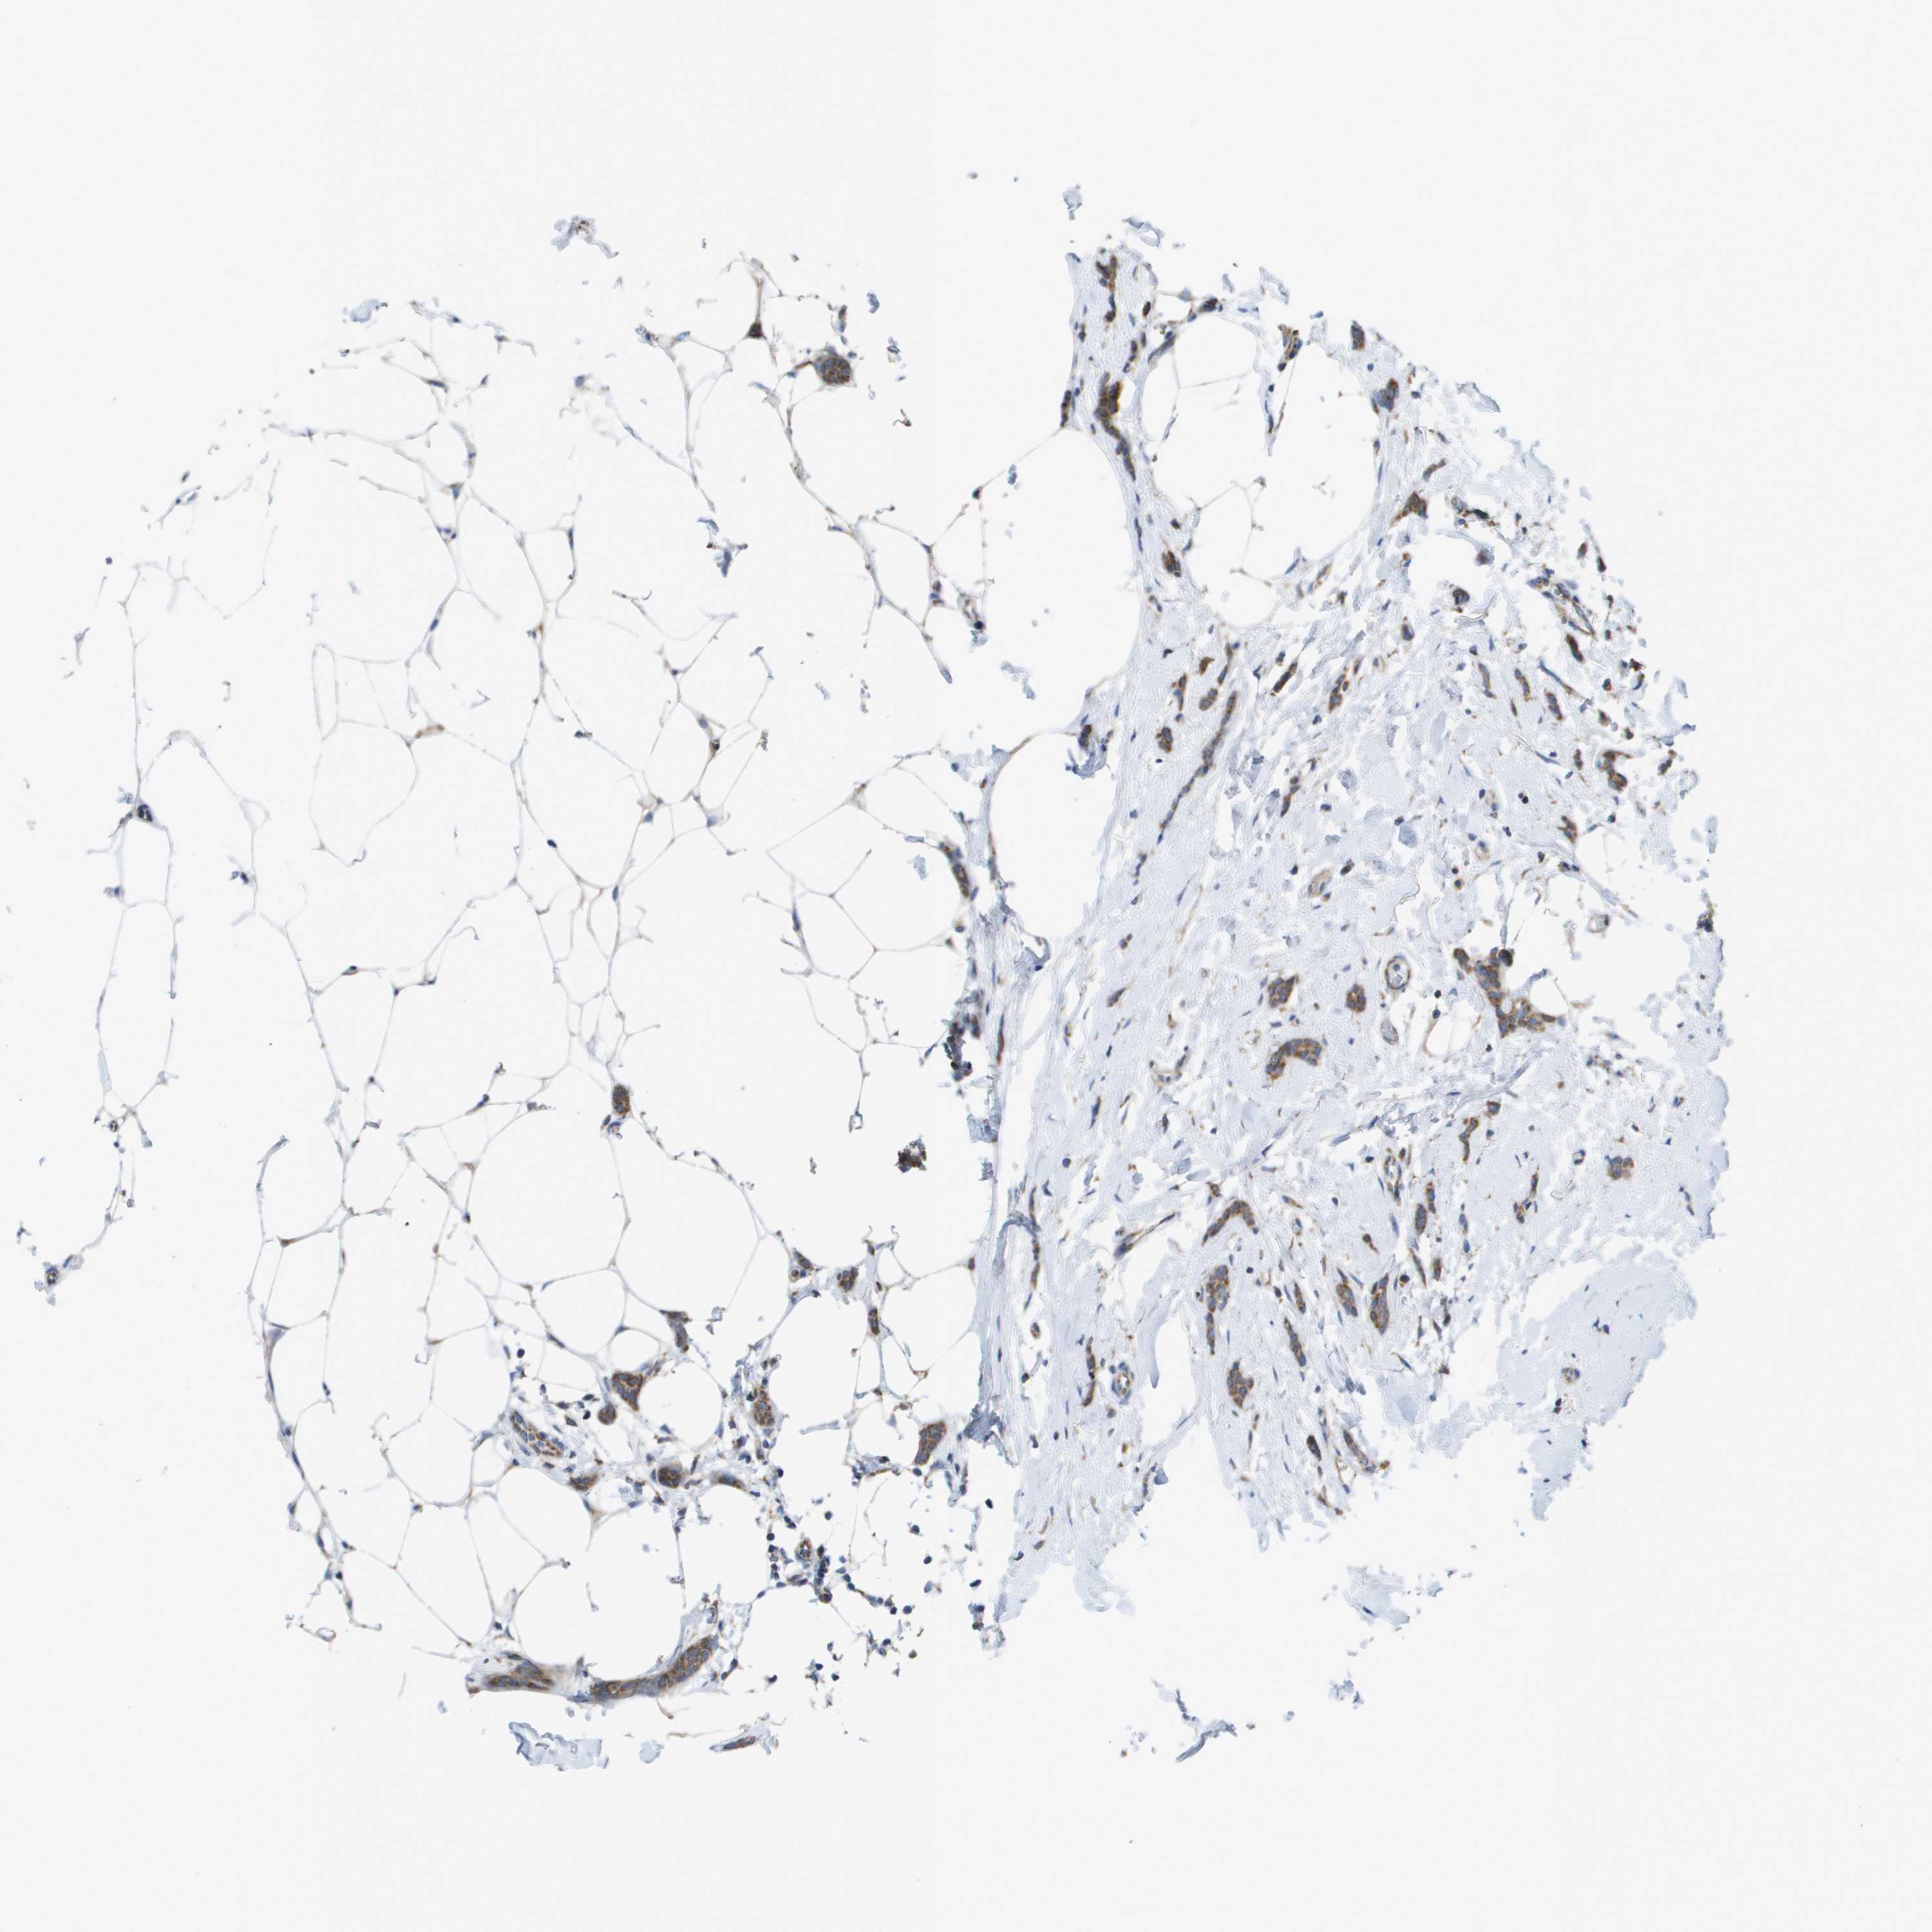

CANCER BREAST CANCER Show tissue menu

BRCA TCGA BRCA VALIDATION PROTEIN EXPRESSION

ANTIBODIES

AND

VALIDATION